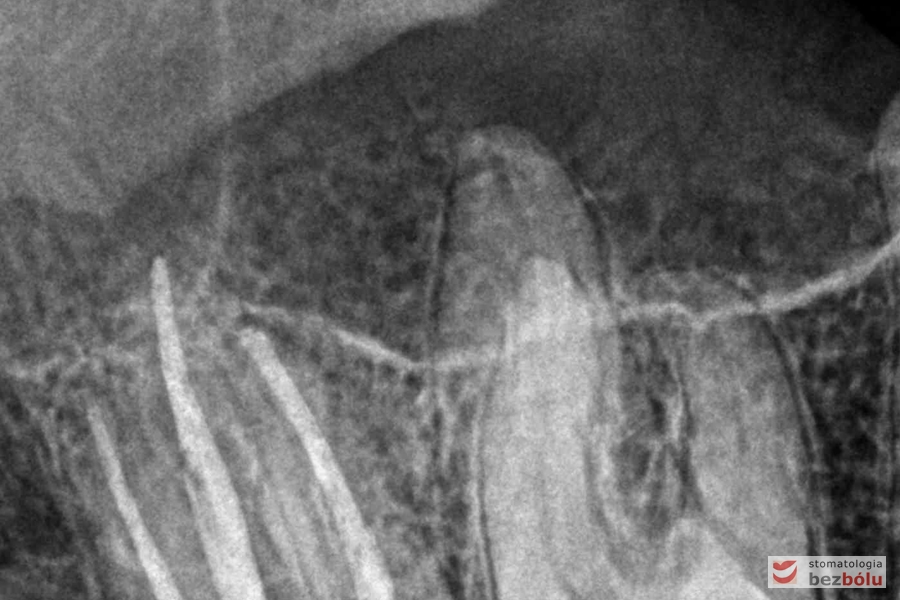

Diagnostyka radiologiczna - przetrwały ząb mleczny w żuchwie, brak zawiązka stałego

Diagnostyka radiologiczna – przetrwały ząb mleczny w żuchwie, brak zawiązka stałego

Kontrola radiologiczna - ocena szczelności wypełnionych kanałów korzeniowych

Kontrola radiologiczna – ocena szczelności wypełnionych kanałów korzeniowych